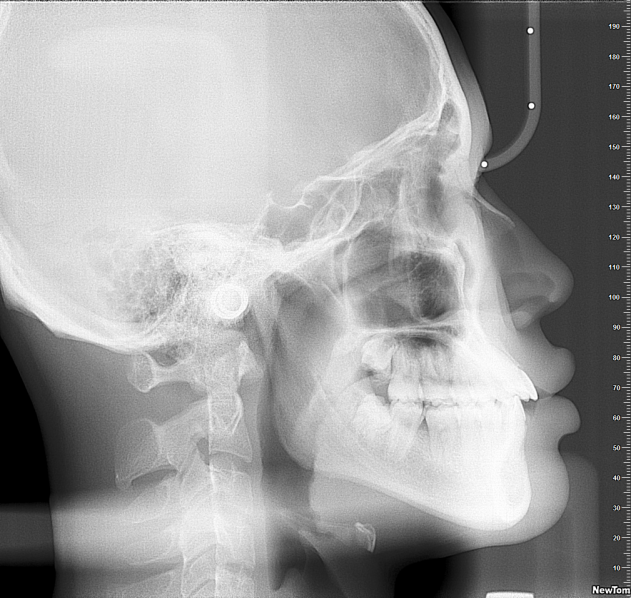

曹显介绍,目前最常见的几种需要牙齿矫正的情况包括牙齿不齐、“地包天”以及龅牙,他以“地包天”举例:“如果下颌往前伸,我们可以通过整牙来将其恢复到正常状态。”

也是因此,正畸是一个“牵一发而动全身”的矫正过程,“整牙的专业术语其实叫‘牙合重建’,相当于把房子推倒一半后重建,让其兼具美观与功能实现。”他特别提到,矫正从来都不仅仅关乎一两颗牙齿,“比如有家长说能不能只调整特别糟糕的牙,这就不符合正畸的操作了。”